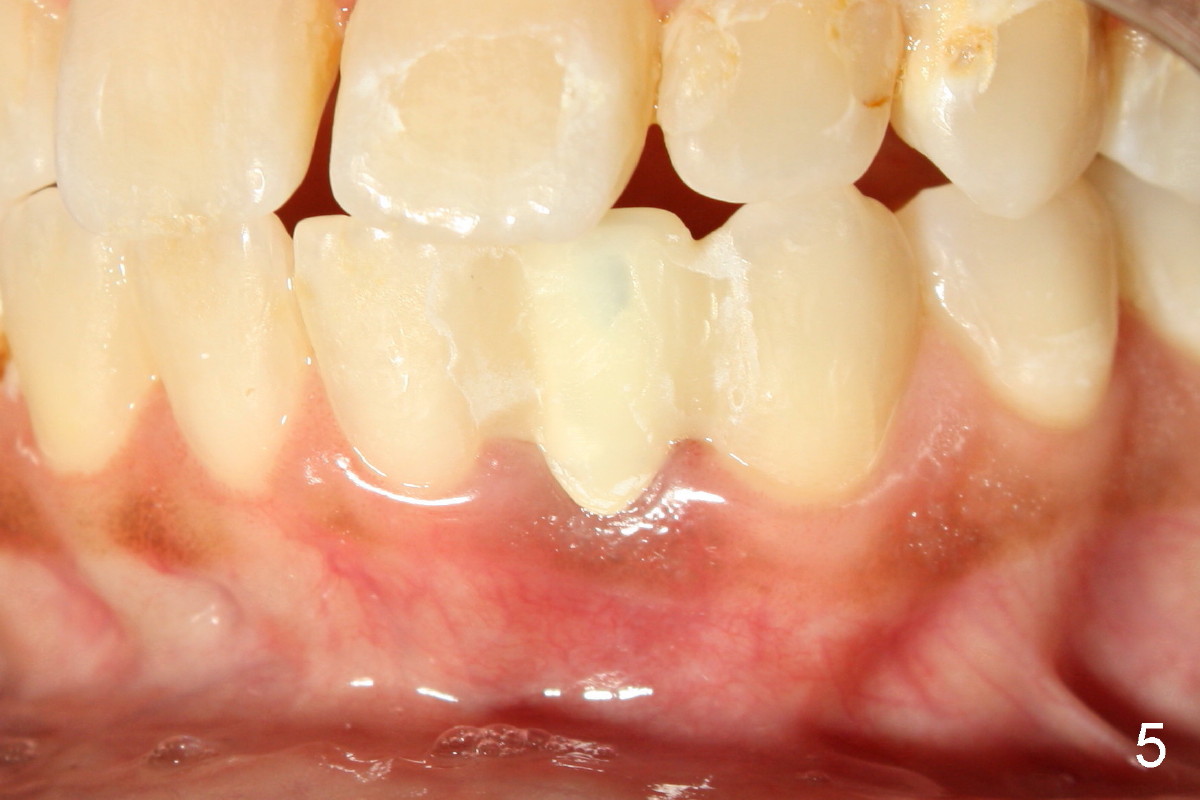

A 44-year-old black lady with ortho several years ago requests fixed restoration for #23 with narrow mesiodistal width (Fig.1). Treatment options are proposed: fixed prosthetic denture and implant. After discussion of advantages and disadvantages of each option, the patient agrees to have implant restoration. A 1.5 mm pilot drill is used to create osteotomy (Fig.2,3). After using 2.0 mm and 3.0 mm tapered osteotomes through the cortex at the crest, 3x17 mm 1-piece implant is placed (Fig.4) and temporary crown is immediately cemented with no centric or lateral occlusion. The patient is doing fine postop, although there is very mild percussion involving the tooth #24, three days postop. Fig.5 and 6 show that the temporary crown is bonded to the neighboring teeth interproximally and lingually. Retrospectively, ortho should have been done to torque the root of the tooth #22 prior to implant placement. Fig.3,4 show that there is space between #21 and 22.